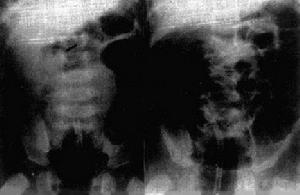

急腹症正確的治療依賴於正確的診斷,而正確的診斷又依賴於全面的收集病史資料及進行多方面的檢查。影像檢查是臨床檢查方法之一。隨著新型X線診斷機的套用及造影技術的不斷改進和更新,它在疾病診斷中的地位也不斷提高。在急腹症的診斷中也是如此。例如:發現膈下游離氣體,結合臨床表現對診斷腹部空腔臟器穿孔有決定性意義。腹部影像中出現擴張的腸管積液平面,應當首先考慮是否存在腸梗阻。值得提出的是影像檢查不僅是一項重要的診斷方法,而且對某些急腹症,如套迭的治療也有著重要的作用。因此,提高醫務人員的診療水平,就需要X線醫生與臨床醫生的密切配合,才能達到一個高質量的診斷標準。

一般急腹症利用腹部平片或透視即可作出診斷,但對一些非典型患者,處於急性期、慢性期的病人,可以針對性的選用一些特殊檢查(如CT、MR等)。

急腹症的常規檢查包括:透視:由於某些胸部疾患,如肺炎、胸膜炎、肺梗塞、氣胸等可能產生一些類似急腹症的症狀,而急腹症又容易繼發一些胸部改變,如肺底炎症、線樣不張、膈肌位置及動度的變化等。因此,在急腹症的影像檢查中,胸腹部的聯合透視是不可缺少的,檢查時,應注意膈肌運動及心臟搏動。腹部積液及其分布與程度,膈下有無游離氣體等。機械性腸梗塞病人腸蠕動亢進,在螢幕上可以看到由於蠕動亢進所致的腸內氣液平面的變化,由低到高或由高到低的反覆升降,有時候還能看到所謂的沸水征,同時結合觸診、血常規檢查,白細胞上升,嚴重感染者可達20.0×10.9/L,甚至出現電解質的紊亂以及症狀表現,這對診斷會有很大幫助。